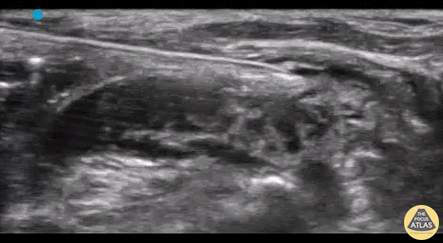

The superficial cervical plexus block pictured above was utilized in an elderly awake patient with dementia for the placement of an IJ CVC. Other indications include I&Ds of submandibular abscesses, lac repair to the ear lobe, and clavicular fractures. The block is best performed in-plane so as to directly visualize the dissection of the plane between the Sternocleidomastoid muscle (visualized superiorly) and the scalene muscles (visualized inferior to the needle insertion), and works by bathing several nerve branches at once. The area of anesthetic overlies the sternocleidomastoid muscle from the clavicle up to the preauricular space and oddly enough, includes the earlobe. Authored by Dr. Nicole Anthony and Dr. Kelly Maurelus, Kings County Medical Center